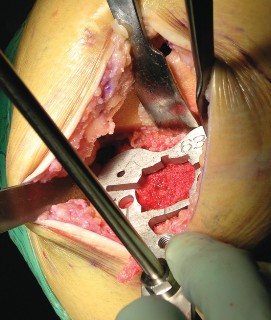

Cementing Technique and Implant Implantation

The hallmark of a cemented TKA is the creation of a durable, interlocking micro-mechanical bond between the host trabecular bone and the polymethylmethacrylate (PMMA) bone cement. PMMA is not an adhesive; it functions as a grout. Therefore, meticulous bone bed preparation is the single most critical factor in preventing aseptic loosening. The resected bony surfaces must be aggressively cleansed using pulsatile lavage to remove marrow, fat, and debris, exposing the porous cancellous bone. Sclerotic areas should be perforated with a small drill bit to enhance cement interdigitation.

The bone must be thoroughly dried immediately prior to cement application. High-viscosity cement is typically mixed under a vacuum to reduce porosity and increase fatigue strength. The cement is applied during its "doughy" phase to both the implant surfaces and the prepared bone. The components are then impacted into place.

Crucially, the cement must be pressurized into the cancellous bone to achieve a penetration depth of 3 to 4 mm. Once the components are seated, all extruded peripheral cement must be meticulously removed with a curette, particularly from the posterior aspect of the condyles and the posterolateral corner, where retained cement fragments can cause severe postoperative pain, third-body wear, or impingement. The knee is then held in full extension with axial compression applied until the exothermic polymerization process is complete and the cement is fully cured.